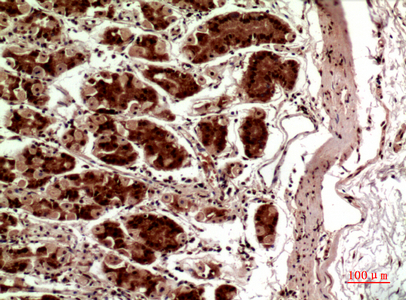

- Scientific DescriptionRabbit polyclonal antibody to TERT.